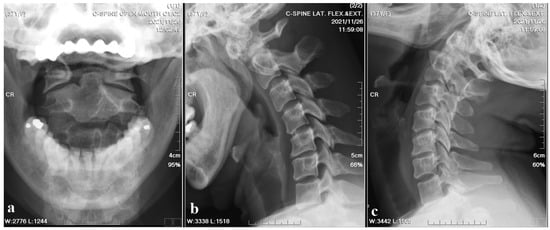

A 37-year-old female with no prior medical history or spinal surgeries presented to our neurosurgery outpatient department five months after a motorcycle traffic accident. Initially diagnosed with a C2 fracture at a local emergency department, she received only conservative treatment and wore a neck collar. Subsequent to the accident, she experienced persistent neck pain radiating to both shoulders and upper back, right-hand numbness with associated weakness, headaches, neck stiffness, and an unsteady gait. An initial cervical spine X-ray revealed the asymmetric widening of the distance between the right C1 arch and the dens with suspected atlantoaxial subluxation (Figure 1). Computed tomography revealed non-fused bony elements (Figure 2). Further cervical spine magnetic resonance imaging (MRI) (Figure 3) highlighted os odontoideum with C1-C2 subluxation and slight spinal cord atrophy at the C1-C2 level due to instability. There was also evidence of ventral compression at the C1-C2 level from chronic inflammatory pannus and granulation tissue.

Figure 1. Cervical spine X-ray images. (a) Open mouth view revealed the asymmetric widening of the distance between the right C1 arch and the dens with suspected atlantoaxial subluxation. (b,c) Flexion and extension also showed suspected atlantoaxial subluxation.